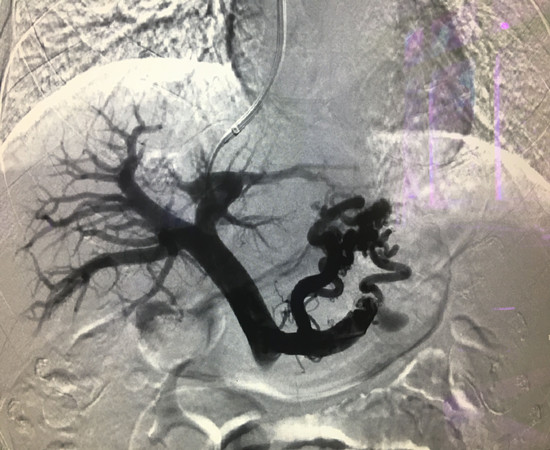

翁某是一位66岁肝硬化失代偿患者,因“肝硬化门脉高压食管胃底静脉曲张破裂大出血”入院,入院前呕血约800ml,入院后当晚呕血约1200ml,病情十分危重,随时都有生命危险,在经过消化内科主任、主管医师黄森林医生及放射介入科张主任等讨论,再征求患者家属同意后决定为患者实施TIPS手术方案。此次手术经颈静脉入路至肝静脉,进行肝内穿刺再进入门静脉建立人工通道,在导丝引导下将导管插至曲张的胃冠状静脉、胃短静脉,将其完全封堵,最后在人工通道处置入支架连接门静脉与肝静脉汇入下腔静脉。术中患者出现上腹部不适、恶心,并呕吐大量鲜血伴血凝块约1500ml,立即给予700ml生理盐水、羟乙基淀粉溶液500ml静脉通道快速输注,快速输血600 ml等紧急处理,经过20多分钟抢救,患者血压稳定、呕血显著减少,失血性休克得到纠正,手术顺利结束。6月7日再次术后回访,患者已能下床走动,情况恢复良好。

TIPS手术创伤小,安全性高,对肝功能影响小,降低门脉压显著,适用于一些危重和失去手术机会的晚期肝硬化合并食管胃底静脉曲张大出血患者。而此项手术的开展,成功填补了我县在肝硬化门静脉高压、食管胃底静脉曲张治疗方面的一项空白。(放射科 刘姝姝)